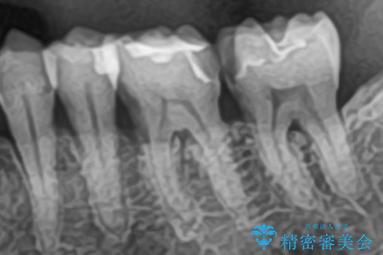

- 左下4番・5番をセラミックインレー、左下6番・7番をセラミッククラウンにより修復する集中治療を計画しました。初回に古い修復物や虫歯を除去し、精密な形成と型取りを行います。2回目に作製したセラミックインレーおよびクラウンの適合・色調を確認し、仮着を行って噛み合わせの微調整を実施します。最終3回目で調整後のセラミック修復物を完全に接着装着して治療を完了します。

今回は左下奥歯の審美性と機能性を同時に回復するため、集中治療を実施しました。左下4・5番の比較的小さな虫歯は歯質保存の観点からセラミックインレーを、左下6・7番は強度確保と噛み合わせへの負担を考慮しセラミッククラウンを選択しました。セラミックは審美性だけでなく、生体親和性も高いため、歯ぐきへの負担も少なく安全に長期使用が可能です。来院回数を3回に集約することで、患者様の負担を軽減しつつ高品質な修復を実現しました。治療後は噛み合わせの改善はもちろん、口元全体の印象が自然で美しい仕上がりとなりました。